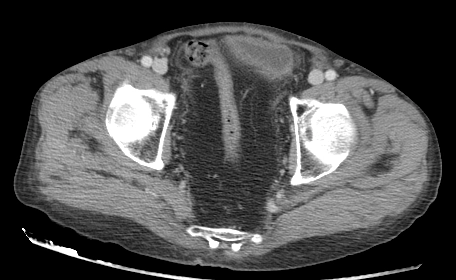

Tích tụ mỡ vùng chậu(Pelvic lipomatosis)

16/03/2026